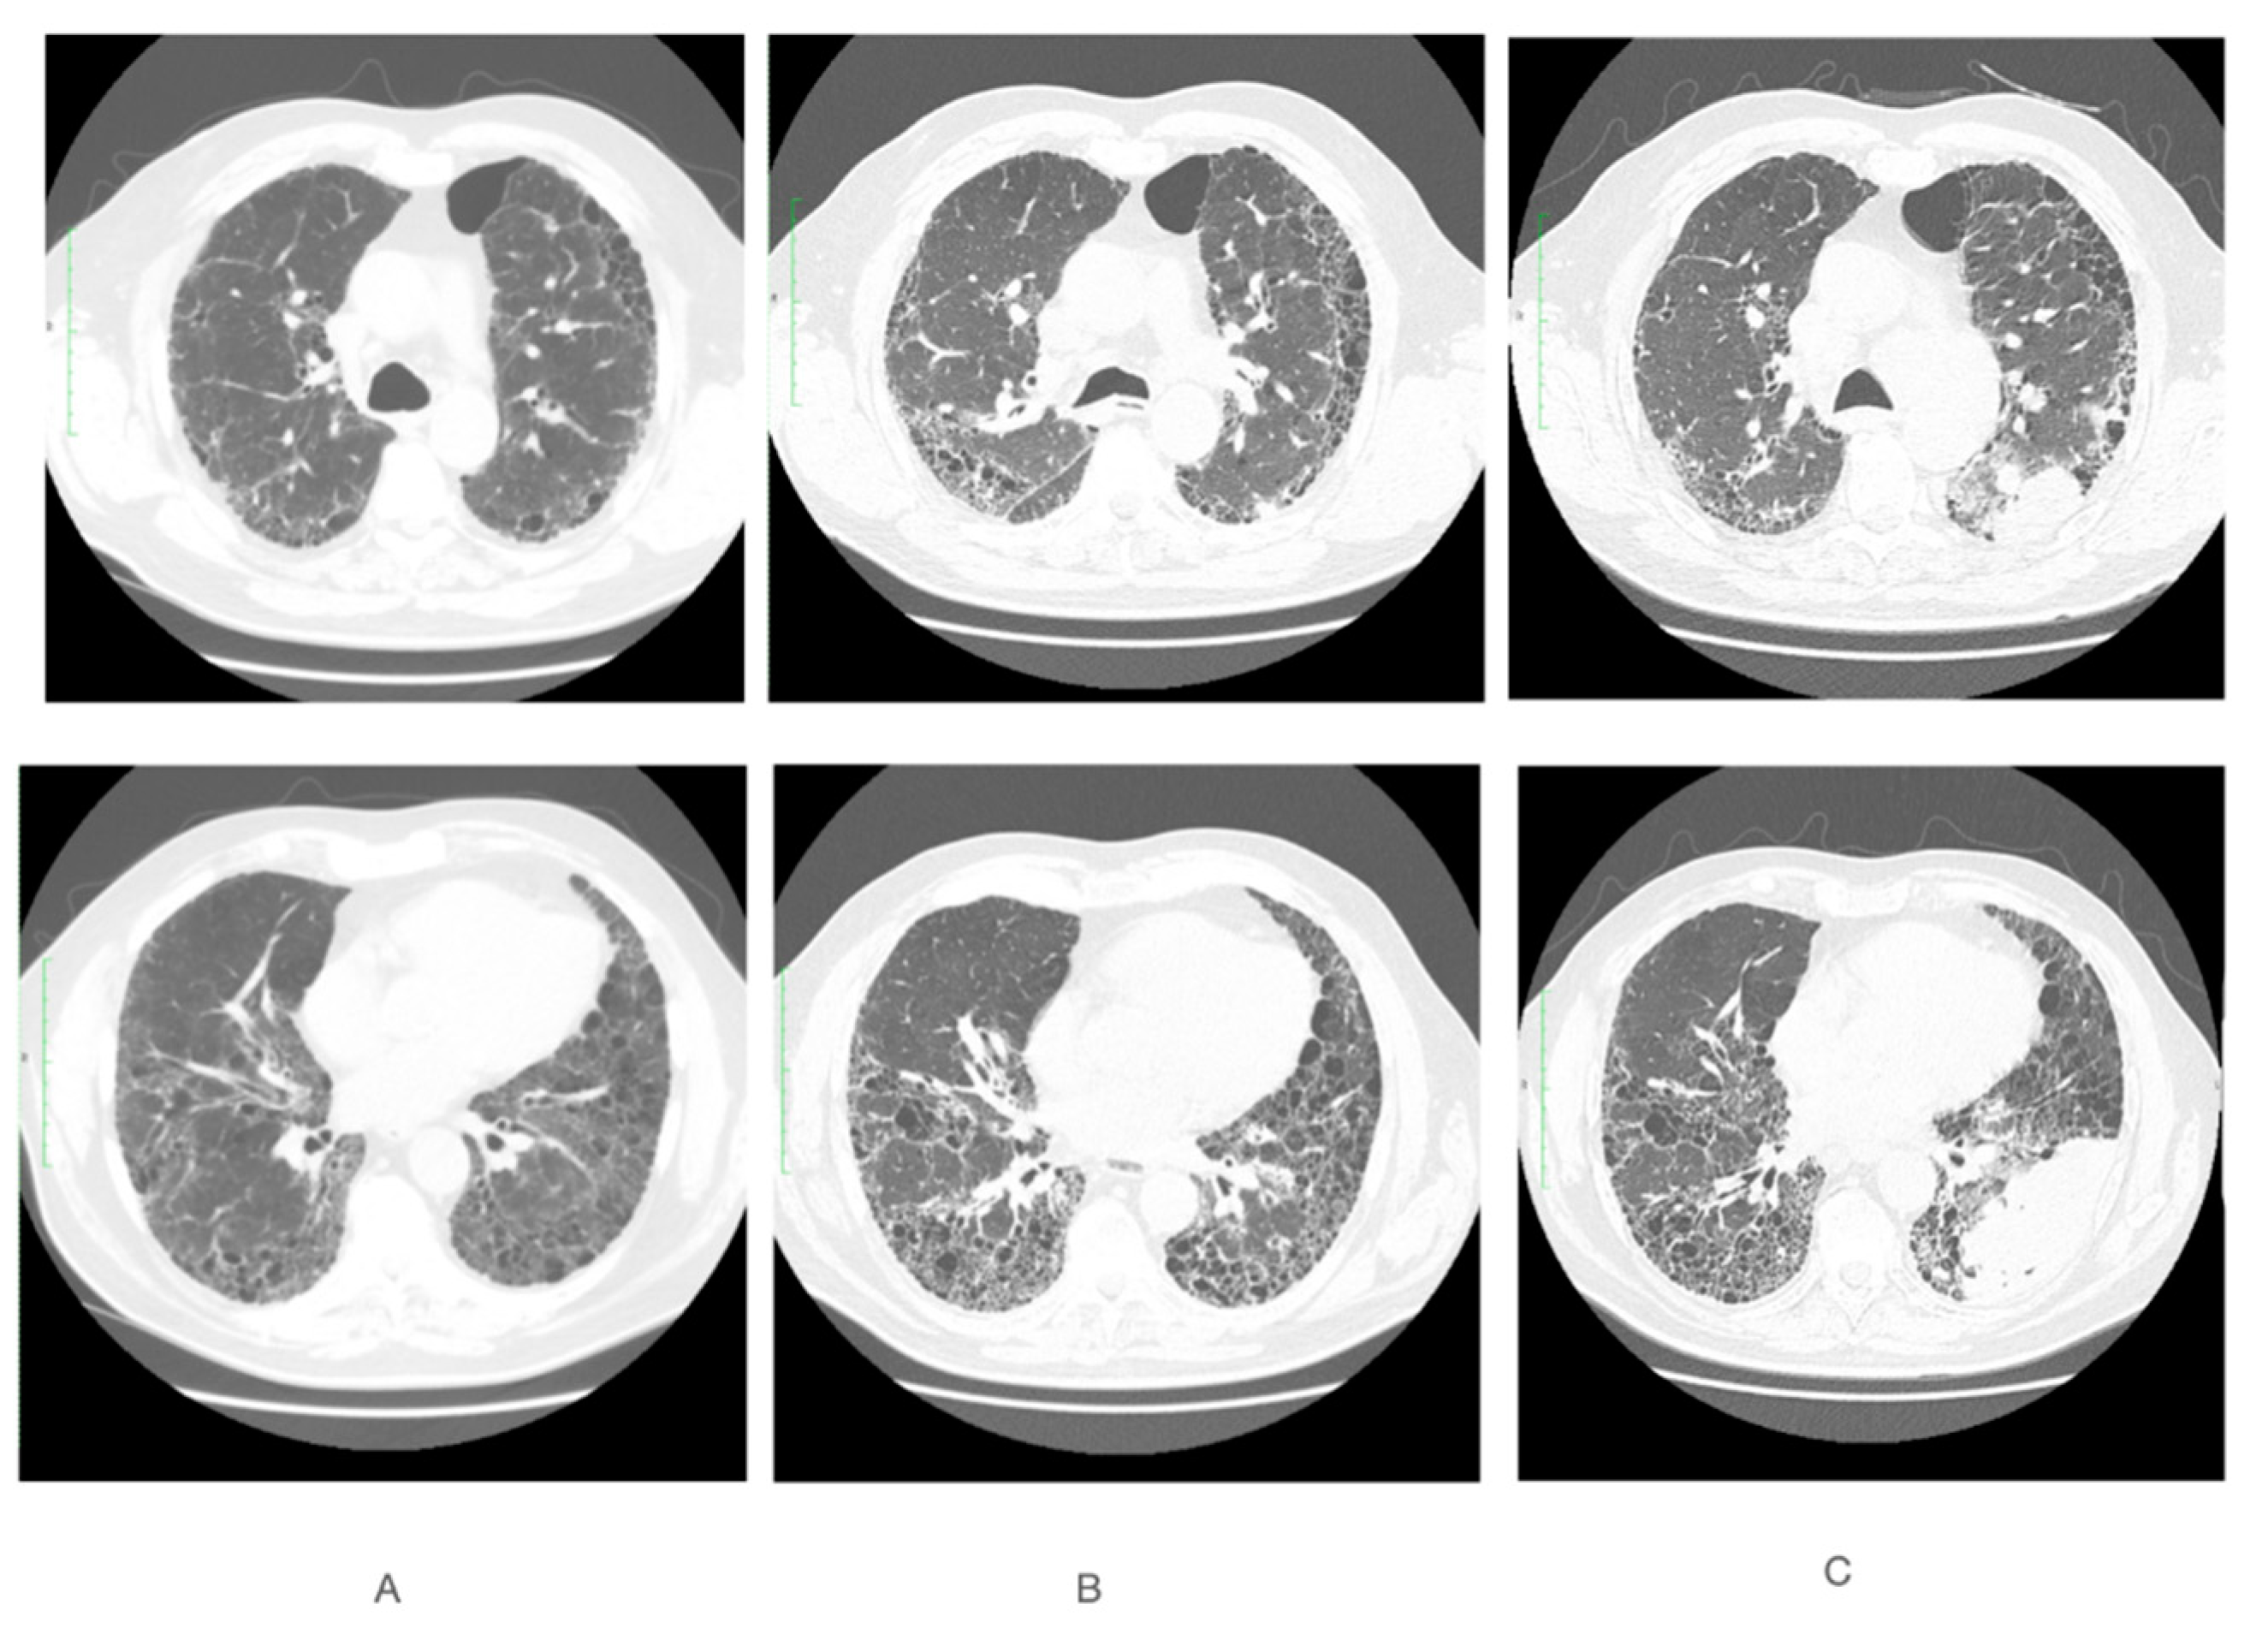

2. Case Report